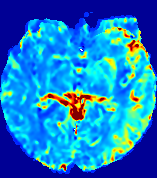

Slice #1Slice #2Slice #3Slice #4Slice #5Slice #6𝐕gt𝟐subscriptnormsuperscript𝐕gt2\|\bf{V}^{\text{gt}}\|_{2}Refer to captionRefer to captionRefer to captionRefer to captionRefer to captionRefer to caption𝐕est𝟐subscriptnormsuperscript𝐕est2\|\bf{V}^{\text{est}}\|_{2}Refer to captionRefer to captionRefer to captionRefer to captionRefer to captionRefer to captionRefer to caption1.51.51.51.21.21.20.90.90.90.60.60.60.30.30.30.00.00.0(mm/s)𝑚𝑚𝑠(mm/s)Destsuperscript𝐷estD^{\text{est}}Refer to captionRefer to captionRefer to captionRefer to captionRefer to captionRefer to captionRefer to caption0.0150.0150.0150.0120.0120.0120.0090.0090.0090.0060.0060.0060.0030.0030.0030.0000.0000.000(mm2/s)𝑚superscript𝑚2𝑠(mm^{2}/s)

Figure 14: PIANO identifiability testing: advection imaging via advection-diffusion. Top row shows 𝐕gt2subscriptnormsuperscript𝐕gt2\|{\bf{V}}^{\text{gt}}\|_{2} used for simulating ground truth pure advection. Rows below show the estimated 𝐕est2subscriptnormsuperscript𝐕est2\|{\bf{V}}^{\text{est}}\|_{2} and Destsuperscript𝐷estD^{\text{est}} on corresponding slices. Note that the plotted value scale for Destsuperscript𝐷estD^{\text{est}} is 0.01 of that for 𝐕gt2subscriptnormsuperscript𝐕gt2\|{\bf{V}}^{\text{gt}}\|_{2} and 𝐕est2subscriptnormsuperscript𝐕est2\|{\bf{V}}^{\text{est}}\|_{2}.

We use the same ‘Advection Imaging’ simulation of Sec. 4.2.1 as the concentration dataset for PIANO. However, instead of modeling pure advection (Eq. 15), we let PIANO estimate both velocity 𝐕estsuperscript𝐕est{\bf{V}}^{\text{est}} and diffusivity Destsuperscript𝐷estD^{\text{est}} via the advection-diffusion PDE (Eq. 2) underlying the proposed PIANO model. Fig. 14 shows the estimated 𝐕est2,subscriptnormsuperscript𝐕est2\|{\bf{V}}^{\text{est}}\|_{2}, and Destsuperscript𝐷estD^{\text{est}} fields for one patient. Although PIANO has the freedom to estimate both a velocity and a diffusivity field from pure advection, PIANO differentiates well between advection and diffusion: the estimated 𝐕est2subscriptnormsuperscript𝐕est2\|{\bf{V}}^{\text{est}}\|_{2} successfully reproduces the ground truth 𝐕gt2subscriptnormsuperscript𝐕gt2\|{\bf{V}}^{\text{gt}}\|_{2} governing the simulated advection process, just as it already did in the ‘Advection Imaging via Advection’ test (Fig. 12). More importantly, the estimated diffusivity Destsuperscript𝐷estD^{\text{est}} is orders of magnitudes smaller than 𝐕est2subscriptnormsuperscript𝐕est2\|{\bf{V}}^{\text{est}}\|_{2}, indicating the estimated diffusion is negligible compared to the estimated advection, which is highly consistent with the underlying pure advection of the simulated data.